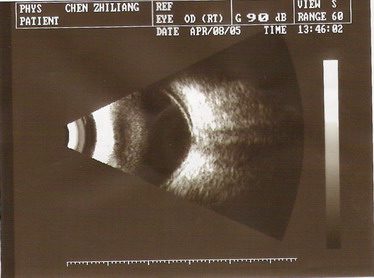

2005年4月8日B超:右眼玻璃体轻度混浊,右眼视网膜脱离,视盘凹陷(青光眼型)